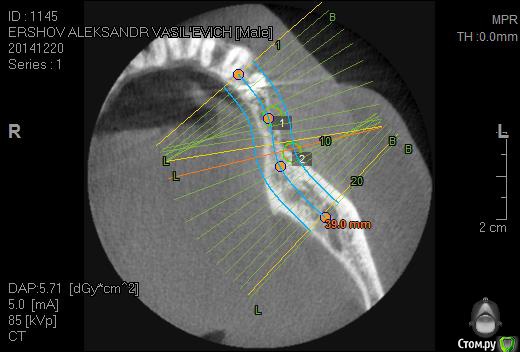

Neilrus Опубликовано 14 января, 2015 Поделиться Опубликовано 14 января, 2015 Здравствуйте. посмотрите мой случай, пожалуйста, и помогите добрым советом. планирую операцию в 3 сегменте импланаты 4,2*10 mis seven по месту 35, 36 зубов, про нехватку костной ткани все понятно, но у меня вопрос к докторам с опытом, можно одномоментно поставить имплантаты как на фотографиях, учитывая форму гребня + МПК (Curved+MP3+ауто со сверла)...или все же не спешить и сделать сначала остеосинтез МПК, а через полгода поставить имплантаты? Как быть конкретно в этой ситауции, когда щечно имплантат будет оголен на половину длины почти, расщепить форма гребня не позволяет ЗАранее спасибо за советы. 35 зуб: 36 зуб (есть риск провалиться, но, мне кажется, кортикалка толстая язычно, должно быть норм) Ссылка на комментарий